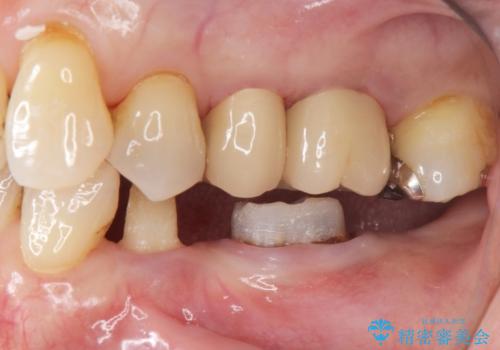

左上56間が狭かったため、写真にはないですが、セパレーションを2回ほど行い、歯根間距離を広げてから処置を行っています。

歯と歯の間(特に歯根と歯根の間)が異常に狭いと歯型が正確にとれない上に歯間ブラシも入らないような歯の形態になり、セルフケアに支障がでてきます。

そのまま無理やり歯型を取って製作するよりも、ご自身で清掃ができる形態にできるため、長期的な予後が期待できます。